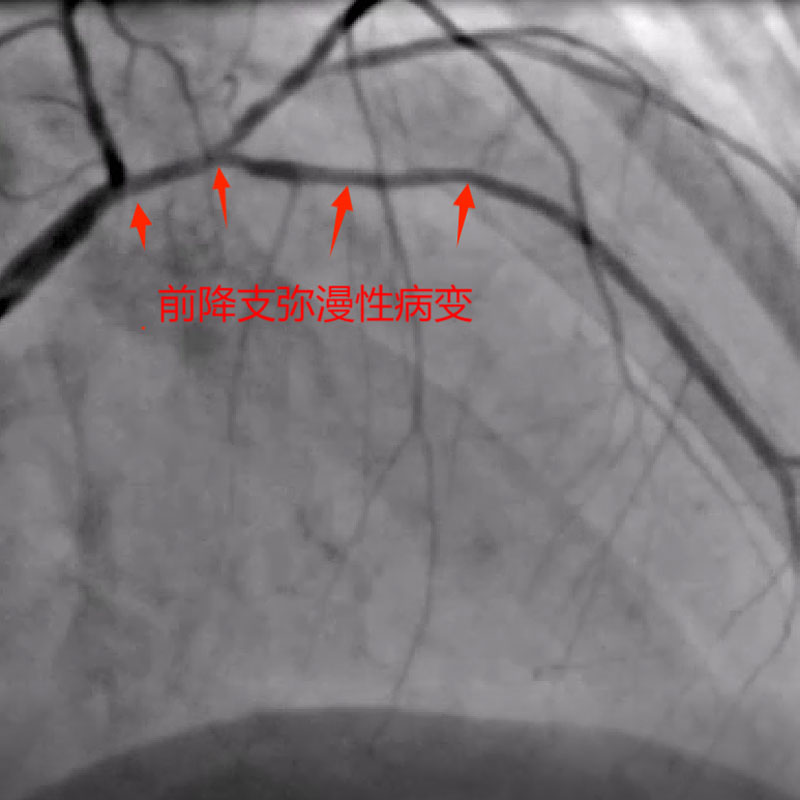

据了解,患者姓田,女性,58岁,本次因间断性胸闷、气促1周于来凤县人民医院就诊。既往有高血压病史多年,入院后评估患者心功能较差,择期冠脉造影提示前降支弥漫性病变伴重度狭窄,对角支粗大,开口严重狭窄,回旋支细小,中度狭窄,右冠轻度狭窄。因患者病情特殊性,心功能较差,多处分叉病变,边支不容丢失,属于高危风险手术人群,手术难度特别大,获得家属同意后,来凤县人民医院心血管内科介入团队决定为患者在IVUS指导下行Crush技术,经过2个半小时努力,成功为患者的分叉病变实行双支架植入。